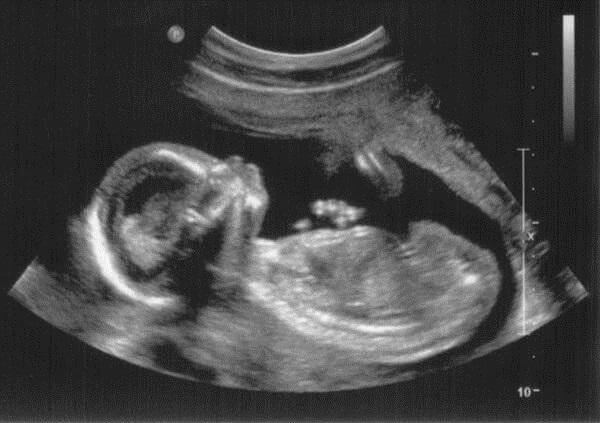

На ранніх термінах лікуючий лікар призначає ультразвукове дослідження, для якого найкраще підходить 6 тиждень вагітності від зачаття. Фото після УЗД стане першим в житті вашого малюка. У вас може не бути ще явного животика, токсикозу або інших ознак цікавого положення, але знімок стане найкращим тому нагадуванням.

Малюк активно рухається, перекидається, стискає і розтискає ручки, це добре видно на УЗІ, але з-за маленьких розмірів мама поки не відчуває ворушінь. На цьому тижні остаточно формуються всі органи. Протягом наступних місяців буде відбуватися їх вдосконалення, сам плід продовжить набирати вагу і рости.

Помилково вважати, що 6 тижнів вагітності від зачаття УЗД-фахівець встановить достовірно. У цього дослідження зовсім інша мета – дізнатися, як розвивається плід і який акушерської тижня відповідає його розмір.